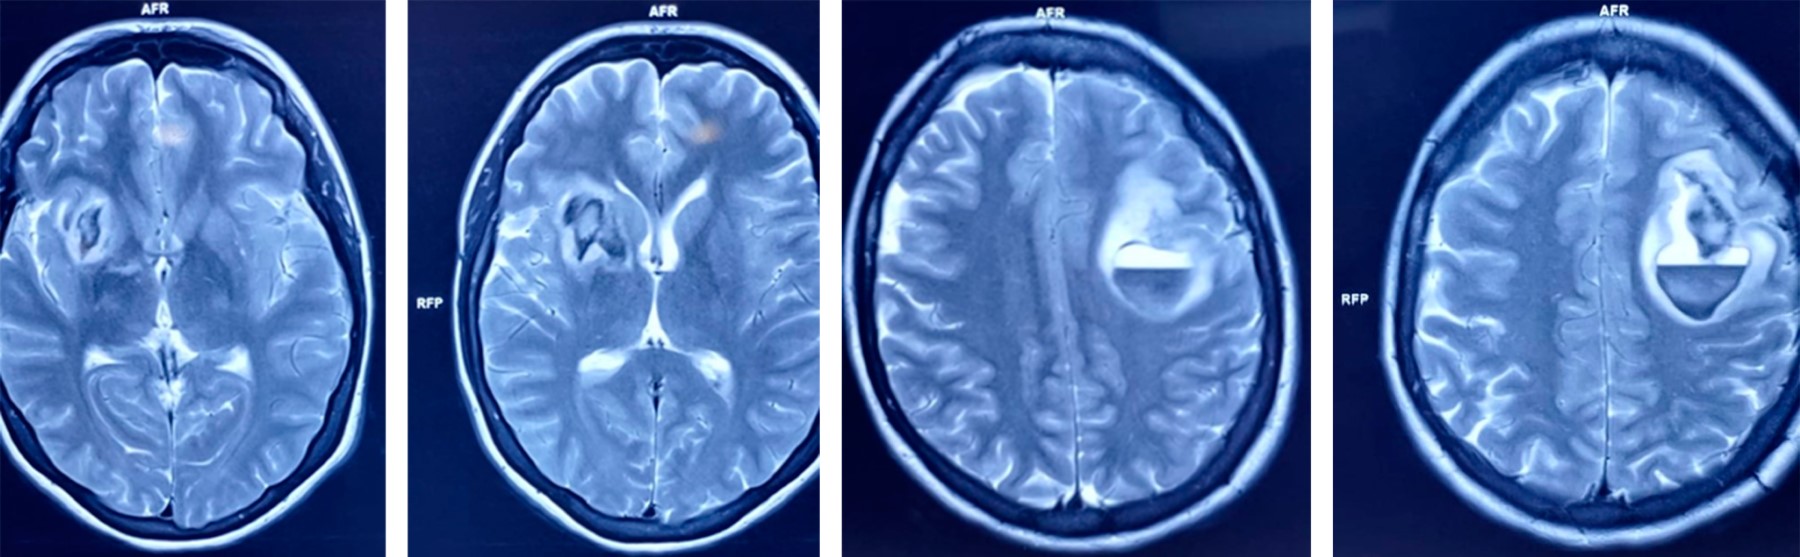

Introduction: primary vasculitis of the central nervous system (PVCNS) is rare, with heterogeneous clinical presentation. Case report: 35-years-old female with seven days with headache, without improvement with analgesics, adding vomiting and stupor, right hemiparesis, and aphasia; CT showed hemorrhages in the right caudate nucleus and left frontal lobe, laboratory tests including antibodies and acute phase reactants normal; pan-angiography showed: a pattern of vasculitis of trunk branches in cerebral arteries and occlusion of the inferior longitudinal sinus; with a diagnosis of possible PVCNS. Drainage of frontal hemorrhage and biopsy was performed, which confirmed the diagnosis; beginning treatment with methylprednisolone bolus and cyclophosphamide, obtaining clinical improvement. Conclusions: PVCNS presents heterogeneous clinical manifestations of acquired neurological deficits; it is a challenge. Its diagnosis implies the existence of the following: a) the acquired neurological deficit, unexplained by another cause, b) angiographic or histopathological evidence of PVCNS, c) absence of systemic vasculitis or other condition that explains it.

Figure 2

Figure 3